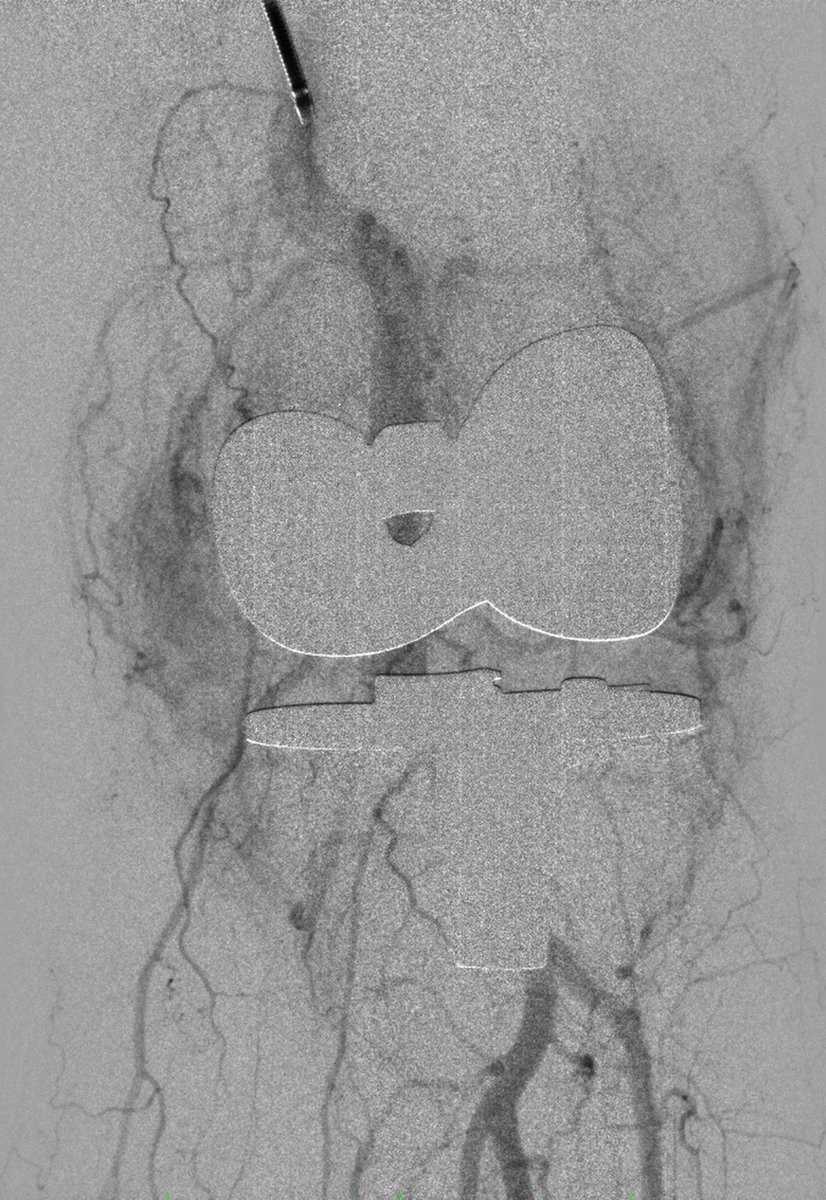

Chock full o'stones! #bph enlarged prostate. #pae an alternative to prostatectomy for gland 250 cc. Mount Sinai IR

live #pae Vascular Inst of VA. Coil rectal (ima inflow) and get distal. Obturator branches to PA and rectum. Mount Sinai IR Ari Isaacson SIR RFS

#PAE week. Sharp medial angles. No problem for new 2F Progreat #terumo Mount Sinai IR Ari Isaacson @UMiamiIR